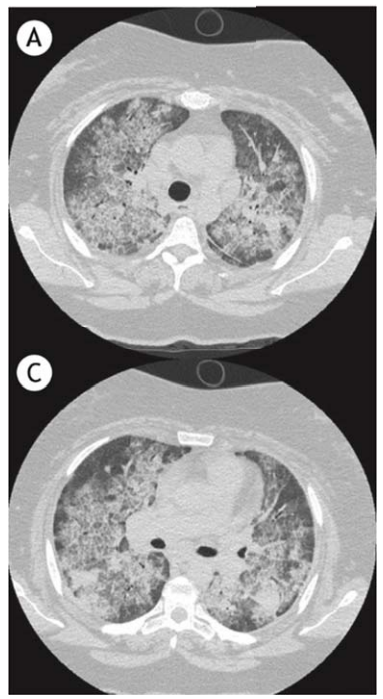

Um homem de 44 anos de idade, portador de IC há dez anos, em uso regular de furosemida (40 mg por dia), espironolactona (25 mg por dia), losartana (50 mg por dia) e amiodarona (400 mg por dia), em razão de episódio de taquicardia ventricular sustentada há três anos, ao exame físico, mostrava-se em estado geral regular, com tosse não produtiva, dispneia e ausência de febre, FR de 18 irpm, sat. de O2 de 97% em ar ambiente, FC de 54 bpm e PA de 130 x 90 mmHg, bilateralmente. Foi iniciado um tratamento para insuficiência cardíaca descompensada e introduziu-se ceftriaxone para a infecção pulmonar. Não houve melhora com essas condutas. Realizou-se um estudo tomográfico (mostrado a seguir) e uma biópsia transbrônquica, que mostrou pneumonia intersticial crônica não específica, com moderado infiltrado inflamatório mononuclear no septo alveolar e abundante número de macrófagos nos espaços alveolares.